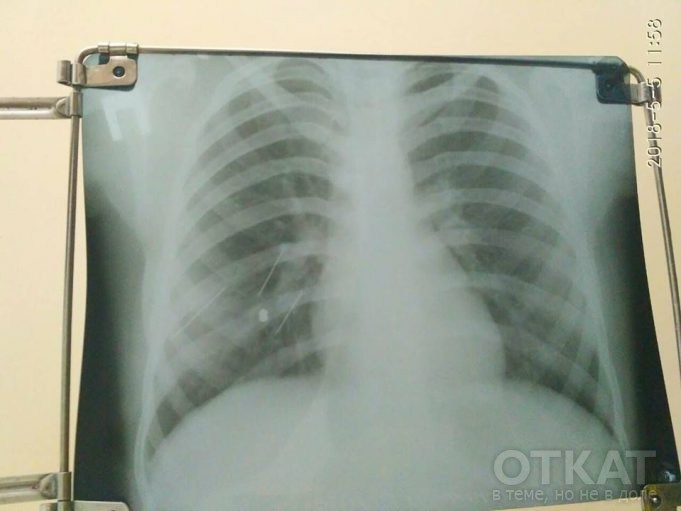

Пуля проникла в легкое, и девочка выжила чудом. ЧП произошло еще 4 мая, однако врачи до сих пор не смогли извлечь пулю из организма ребенка. Очередная операция предстоит на следующей неделе в Киеве.

К слову, пуля, выпущенная в девочку – свинцовая. Свинец, попадая в организм человека, имеет свойство окисляться, нанося тем самым вред.